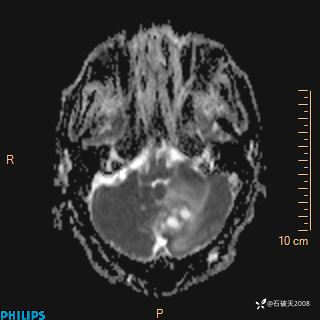

增强轴位